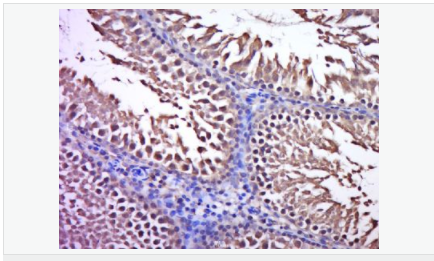

產品應用WB=1:500-2000 ELISA=1:5000-10000 IHC-P=1:100-500 IHC-F=1:100-500 ICC=1:100-500 IF=1:100-500 (石蠟切片需做抗原修復)

細胞定位細胞漿

產品介紹C3orf32 (chromosome 3 open reading frame 32), also known as fls485, is a 353 amino acid protein encoded by a gene that maps to human chromosome 3p26.1. Chromosome 3 is made up of approximately 214 million bases encoding over 1,100 genes. Notably, there is a chemokine receptor gene cluster and a variety of human cancer related loci on chromosome 3. Particular regions of the chromosome 3 short arm are deleted in many types of cancer cells. Key tumor suppressing genes on chromosome 3 encode apoptosis mediator RASSF1, cell migration regulator HYAL1 and angiogenesis suppressor SEMA3B. Marfan Syndrome, porphyria, von Hippel-Lindau syndrome, osteogenesis imperfecta and Charcot-Marie-Tooth disease are a few of the numerous genetic diseases associated with chromosome 3.

Tissue Specificity:

Expressed in enterocytes of small and large intestinal mucosa (at protein level). Expressed in enterocytes, chromaffine and interstitial cells.